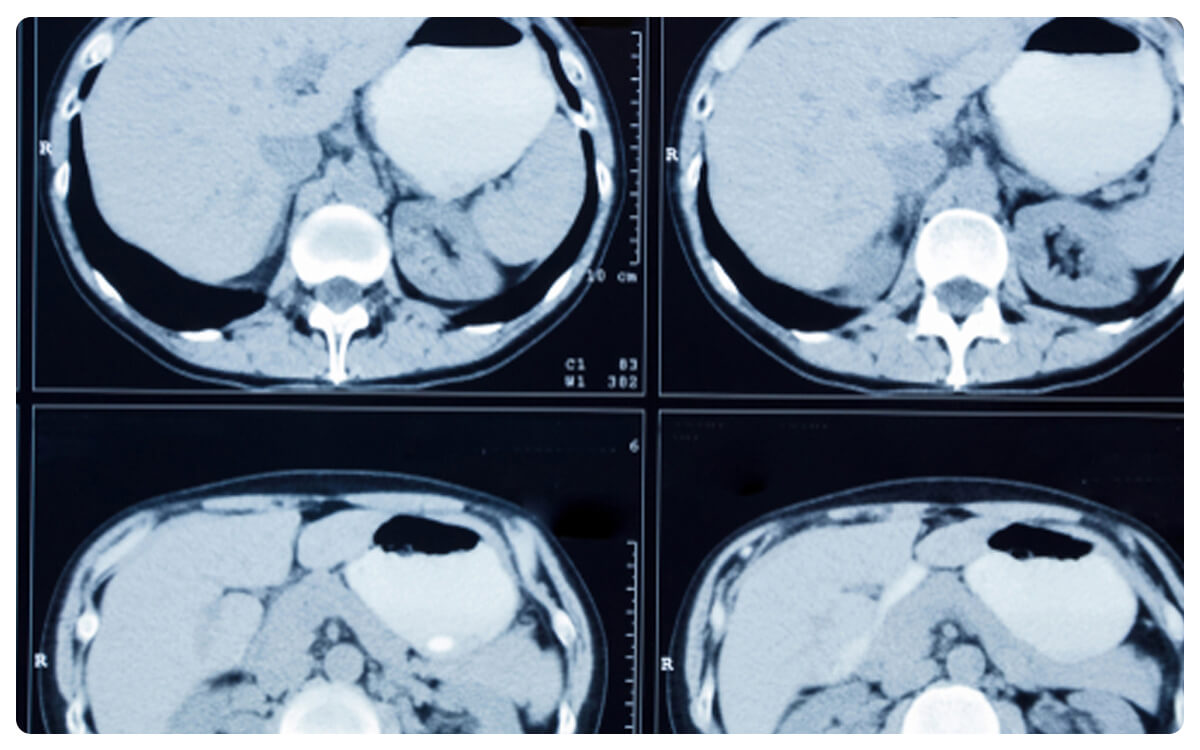

La Tomografía de Score de Calcio Coronario se erige como una herramienta clave en la evaluación de la salud cardiovascular, permitiendo una evaluación precisa y no invasiva de la cantidad de calcio acumulado en las arterias coronarias. A través de imágenes de alta resolución obtenidas mediante tomografía computarizada, esta técnica proporciona un puntaje que refleja el grado de calcificación presente en las arterias, lo que puede ser indicativo de la presencia de enfermedad arterial coronaria.

La Tomografía de Score de Calcio Coronario desempeña un papel crucial en la estratificación de riesgos y el pronóstico de enfermedades cardíacas, brindando información valiosa para la toma de decisiones clínicas informadas y el diseño de planes de prevención y tratamiento cardiovascular.